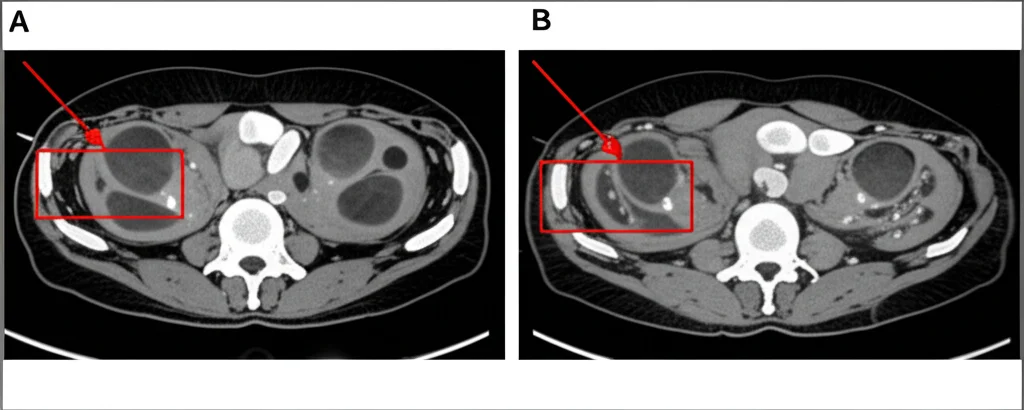

Ma le belle idee vanno testate sul campo, giusto? Ed è qui che entra in gioco uno studio recente che ho trovato particolarmente illuminante. L’obiettivo era proprio valutare quanto fosse bravo Node-RADS a scovare i linfonodi metastatici nel cancro rettale prima di qualsiasi terapia (stadiazione primaria), confrontando direttamente le sue performance su diverse modalità di imaging:

- TC con mezzo di contrasto (CE-CT)

Hanno preso in esame retrospettivamente 113 pazienti con cancro rettale confermato, che non avevano fatto terapie neoadjuvanti e sono stati operati. Due radiologi esperti (ma indipendenti tra loro e all’oscuro dell’esito istologico) hanno valutato i linfonodi regionali usando Node-RADS per ogni modalità. Poi, hanno confrontato i risultati con la verità: l’analisi istopatologica dei linfonodi asportati durante l’intervento.

Ebbene, i risultati sono stati piuttosto netti. Prima scoperta: Node-RADS si è dimostrato significativamente migliore rispetto al solo criterio della dimensione (SAD) in tutte e tre le modalità di imaging. L’Area Sotto la Curva (AUC), un indice che misura la performance diagnostica generale, era più alta per Node-RADS (circa 0.84-0.85) rispetto al SAD (circa 0.74-0.79). Questo conferma che guardare solo quanto è grande un linfonodo non basta, le sue caratteristiche interne e la forma contano eccome!

Ma la vera chicca, secondo me, è la seconda scoperta: non ci sono state differenze significative nella performance diagnostica di Node-RADS tra CE-CT, T2WI e T1CE. Sensibilità (capacità di trovare i malati) e specificità (capacità di identificare i sani) erano molto simili, attestandosi rispettivamente intorno al 76-79% e al 91-93%. Anche l’accuratezza generale era comparabile (86-88%).